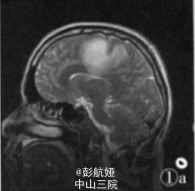

患者,男,34岁。以呼吸困难咳嗽咳痰伴上腹痛1周为主诉于2006年9月25日入院。发病时深呼吸咳嗽后胸口隐痛,痰中带血。血生化检查示:C反应蛋白22.4 mg/L(正常值0—8 mg/L)。心肌酶谱:谷草转氨酶46 U/L,乳酸脱氢酶2085 U/L,磷酸肌酸激酶57 U/L,肌酸激酶同工酶52 U/L,羟定酸脱氢酶192 U/L。凝血检查示:凝血酶原国际标准化比值1.01,凝血酶原正常对照12.90,凝血酶原时间13.0。外院完善寄生虫病原学检查示:痰虫卵(一),血清囊虫抗体弱(+),肺吸虫抗体(一),血吸虫抗体(一)。肿瘤四项检查示:AFP:328.1μg/L,CAl25:1.8μg/L,CAl99(一)。影像学检查示:B超“双乳头下3 cm×3 cm实性肿块,双腋下淋巴结肿大,颈部、手臂内侧、颅侧额叶左侧枕叶多发占位,肺部多发类圆形占位,肝脏脾脏多发占位,考虑为肝癌,颅内及肺内转移,不排除寄生虫病可能”,2006年10月1日行手臂肿块活检。

病理诊断:男性绒毛膜癌,并发肝、肺、脑、手臂转移。本例并发肝、肺、脑、手臂多处转移灶,已经出现胸、腹部症状,经化疗无效,最后出现呼吸衰竭自动出院。